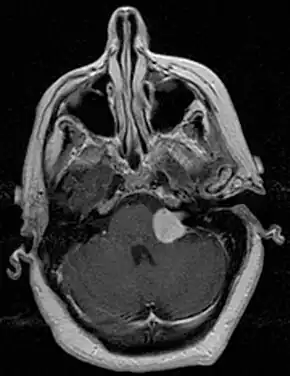

![]() | |

| Bilateral schwannomas in a person with neurofibromatosis 2 | |

Preliminary diagnostic procedures include ear examination, hearing and vestibular testing. The auditory brainstem response test (ABR) is a cost-effective test to see if a VS has perhaps compromised the cochlear nerve. A computed tomography test (CT scan) will show the presence of a VS, although very small tumors may be missed. The 'gold standard' for diagnosis of VS is magnetic resonance imaging, MRI. The NIH consensus statement for VS in 1991 stated: "MRI now is regarded as the most definitive study that can be performed, and is capable of revealing vestibular tumors as small as a few millimeters in diameter."[9] This remarkable technology superseded the CT scan that was in wide use by 1971 despite its ionizing radiation risks. By using thin-slice sectioning and gadolinium dye contrast, MRI scanners can find even the smallest of tumors without the risk of radiation. This is especially important for spotting rare cases of bilateral VSs where one of the tumors is often only a few millimeters in diameter. Spotting previously missed small tumors meant that the average tumor size at diagnosis decreased.